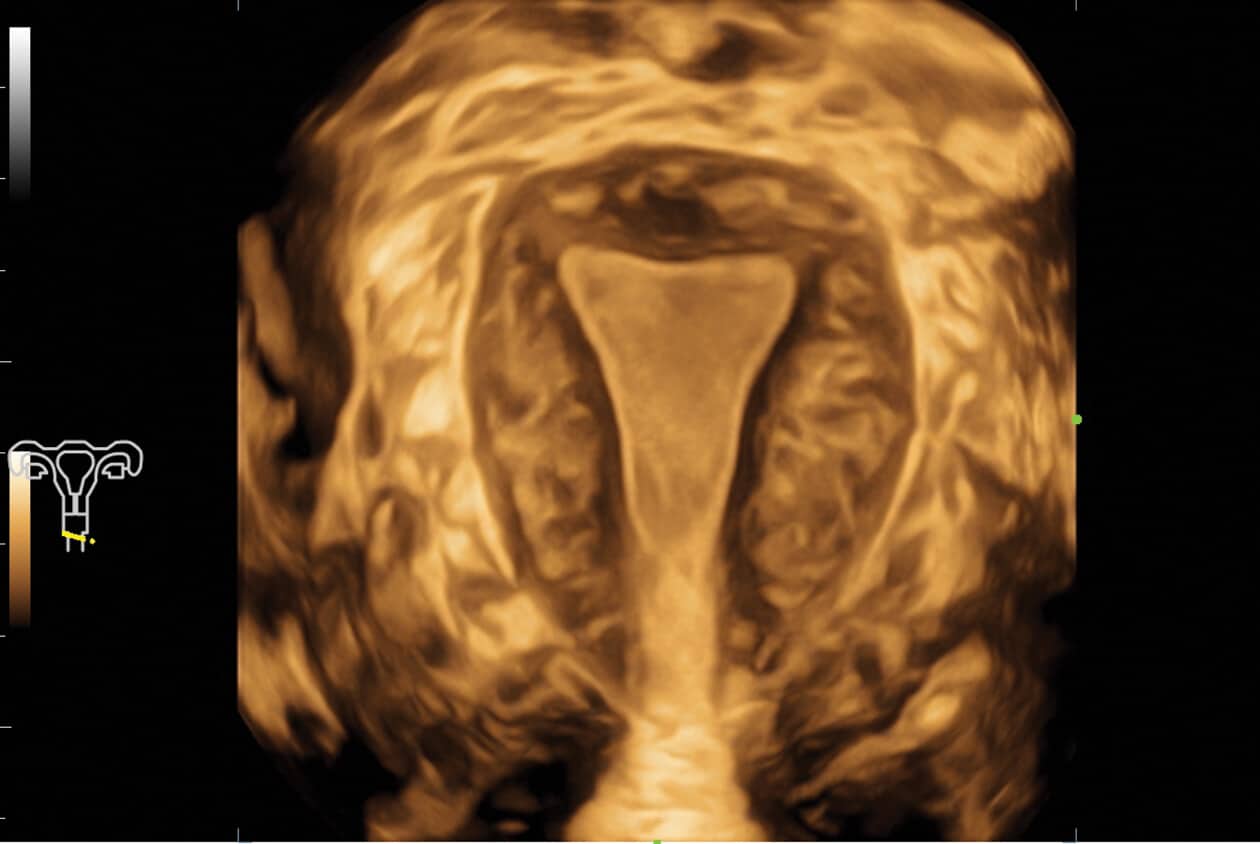

Powered by Mindray’s revolutionary ZONE Sonography (R) Technology+, the Imagyn I9 System boasts advanced ultrasound capabilities and leverages AI-inechanged technologies. The Imagyn I9 starts the process using auto clinical scenario identification, and uses automation at every point, from imaging optimization to planes scenario identification, and uses automation at every point, from imaging optimization to planes acquisition, quantification, and creating an automated workflow. The Imagyn I9 System provides a full-stack smart solution for efficient women’s health, covering wide-ranging applications from pre-pregnancy to obstetric to post-partum.